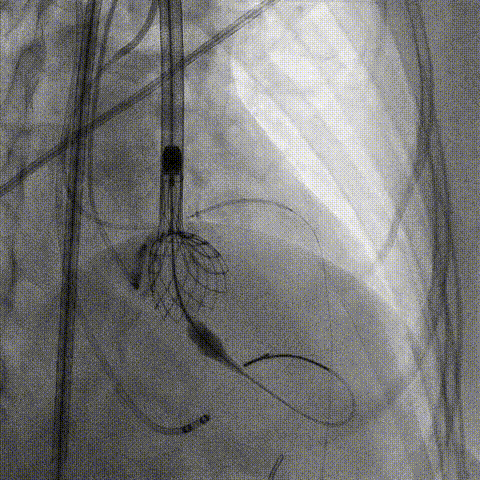

第一次释放

再次评估左冠开口,考虑调整瓣膜深度

回收后调整深度,再次释放

评估左冠开口

左冠开口切线位造影

决定左冠烟囱支架保护冠脉

调整支架位置

释放冠脉支架

释放瓣膜

造影评估

支架内后扩张

冠脉造影

根部造影

最终结果